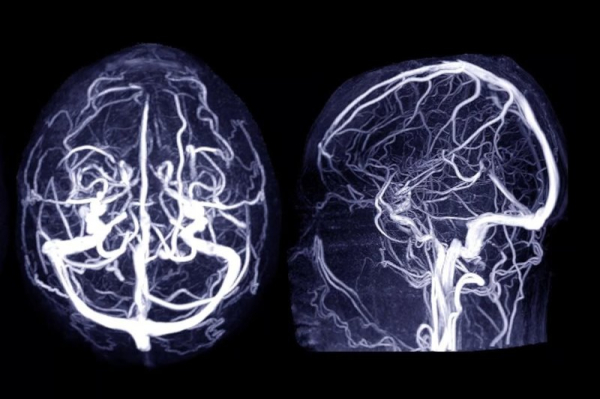

Four common drugs — lisinopril, simvastatin, metformin and tamsulosin — appeared to lower the risk of a brain aneurysm, after accounting for other risk factors. Photo by Adobe Stock/HealthDay News

The researchers evaluated the risk of brain aneurysms that cause bleeding strokes in patients. Advertisement